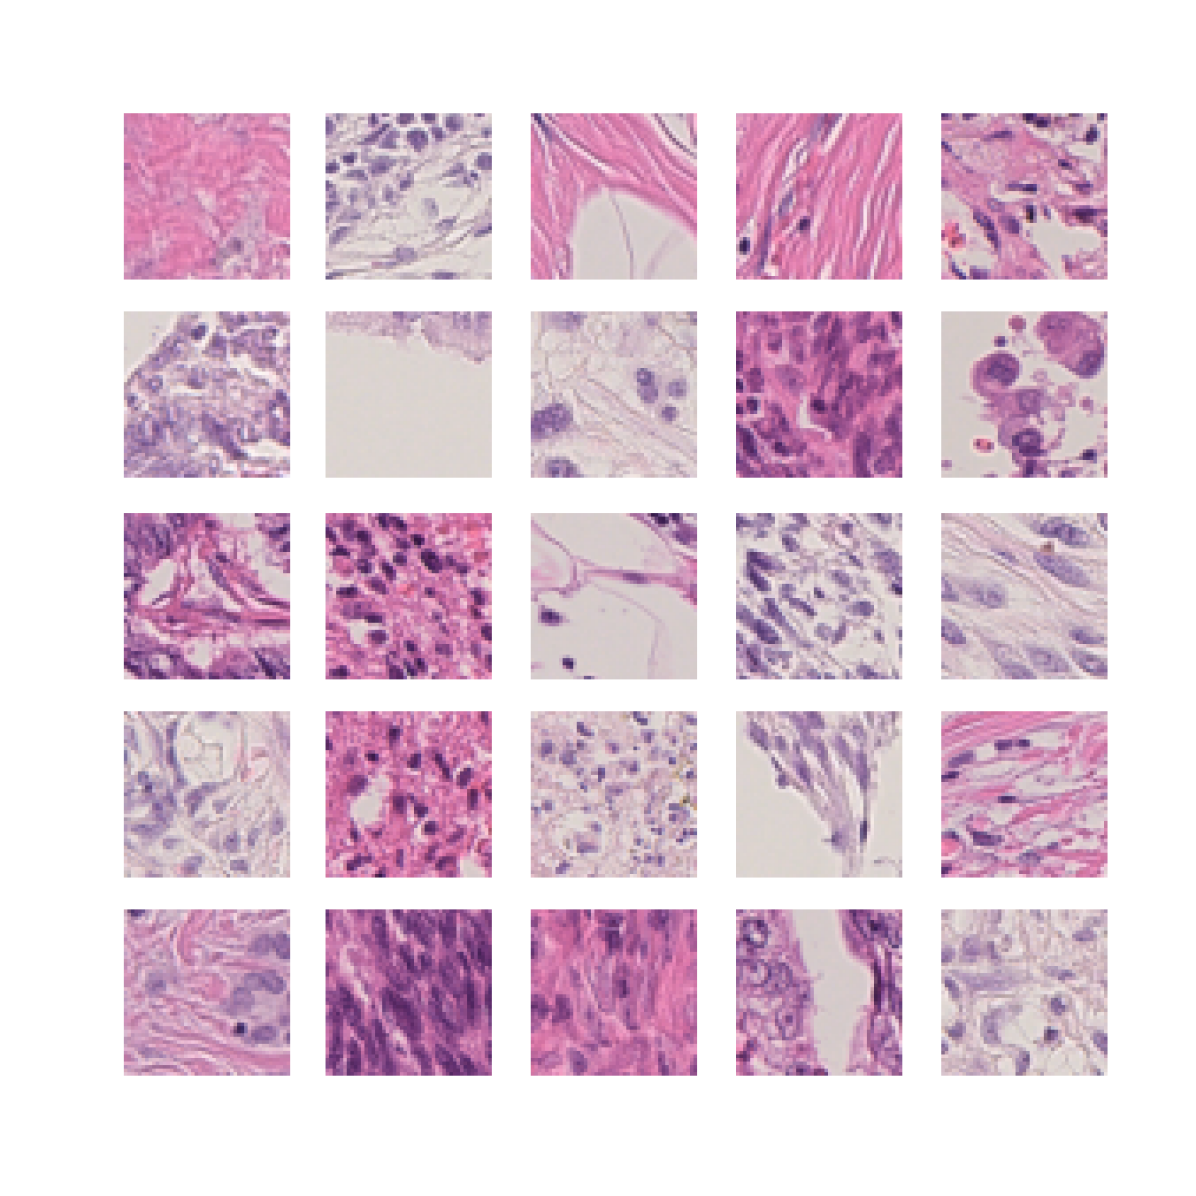

We also analyse the activation maps for each model using GradCAM as described in section S3. This offers more insight into the areas of the image which are contributing most heavily to the models’ representations. In Figure 4(b) we present some representative examples, however, a larger selection which was chosen at random is presented in Figures S10 to S25. The larger selection makes it easier to see the emergent patterns, including that privileged Siamese models tend to mainly identify features which are strongly present in both inputs, while unprivileged Siamese models tend to learn more diffuse features that are not specific to one cell phenotype or image region. TriDeNT ♆ incorporates both sets of features, learning both features specific to the privileged data and more the general features associated with unprivileged Siamese networks.

We can see in Figure 4(b) panel A that for ERG, the privileged Siamese model focuses almost exclusively on any nuclei which could be endothelial cells. As there are very few endothelial cells in the dataset, it could be an effective strategy to identify anything that could potentially be an endothelial cell to minimise the difference between the representations of the H&E model and the IF mask model. In the corresponding unprivileged Siamese image, we see that the model identifies some of these nuclei, albeit less strongly, but also focuses heavily on the other tissue and even the background, while strongly fixating on two spots of debris in the center of the image. This model has less ‘incentive’ to learn the weak features related to endothelial cells as these occur rarely and are not easy to detect, while more generic strong features such as the presence of connective tissue and the prevalence of background are more common and predictable from augmented images. We see that TriDeNT ♆ combines these two feature sets, strongly identifying nuclei while also identifying the connective tissue.

In panel C we see a similar pattern, with the privileged Siamese model fixating solely on the nuclei, while the TriDeNT ♆ model takes a more balanced approach. The unprivileged Siamese model appears to focus on a single cluster of nuclei while neglecting others, and similarly identifies an area of fibroblasts with its distinctive pattern but does not others.

In contrast to panels A and C which represent models with poor privileged Siamese results, panels B and D represent models whose privileged Siamese results were comparable to both TriDeNT ♆ and even the supervised baseline. It is therefore interesting to note that there are far more similarities between the privileged Siamese and TriDeNT ♆ models in both cases. Particularly in panel B, TriDeNT ♆ and the privileged Siamese model return virtually identical heatmaps, with both strongly identifying epithelial nuclei and neglecting the same areas of connective tissue. The unprivileged model in this case appears to focus solely on the centre of the image, giving a significantly different heatmap to the other panels.

Panel D again shows the previous pattern, with the privileged Siamese model identifying the features strongly present in the privileged data – fibroblasts – while neglecting the nuclei present. TriDeNT ♆ also strongly identifies the connective tissue, but, unlike the privileged Siamese model, does not completely neglect the nuclei. The unprivileged Siamese model primarily identifies background, and does not appear to identify the nuclei in this example.